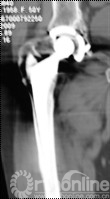

4例因发现腹股沟、或髂窝处渐大、隐痛不适包块而就诊;1例因大腿上外侧出现渐增大无痛性包块就诊;2例术后定期随访拍片发现假体周围局灶性骨溶解,进一步行三维CT扫面发现骨盆内炎性假瘤。所有患者X线片拍片均发现假体周围局灶性骨溶解,假体稳定固定。7例X线发现髋臼DeLee和Charnley II区骨溶解,1例同时伴有股骨侧外侧骨溶解(Gruen II区)。7例三维CT扫描均提示骨溶解区,其中6例CT提示骨盆内软组织包块,1例CT显示大腿前外侧软组织包快(图1)。

图1 CT片示股骨上段GruenII区骨溶解,外侧炎性假瘤形成(箭头所示)